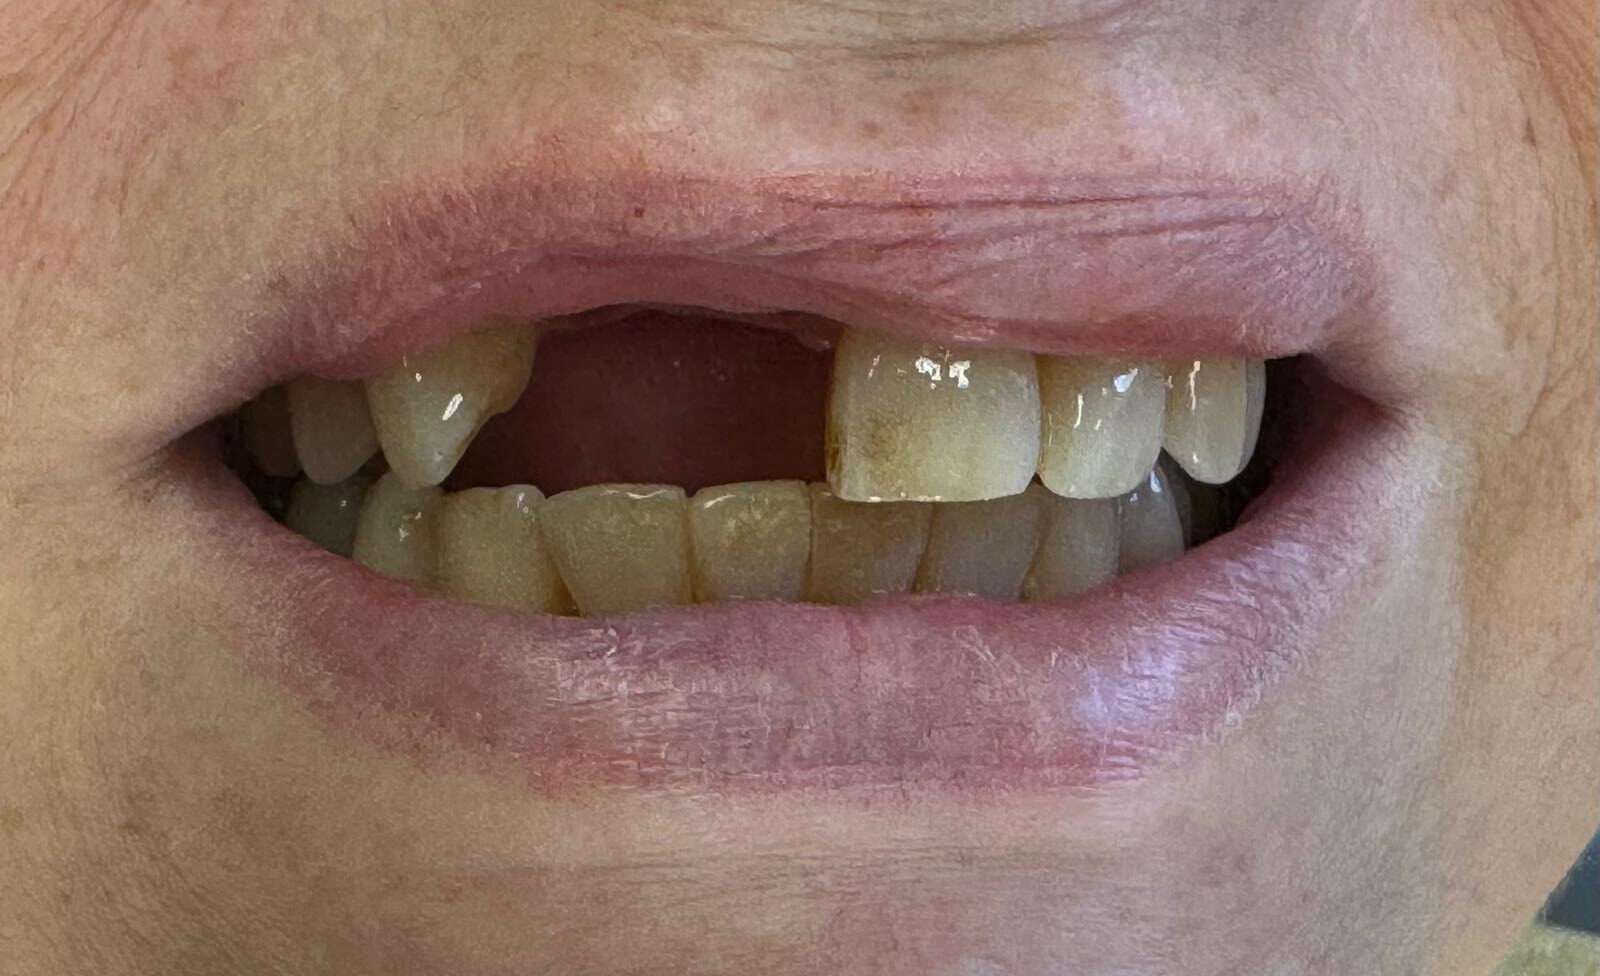

Single Front Implant

Upper right central incisor

Before

After